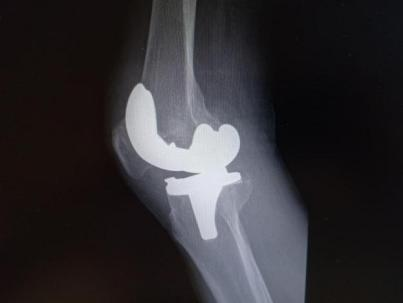

12月17日,贵州航天医院第88次晨读会由我院骨一科主任、副主任医师陈明勇作学术交流,他以“肱骨近端骨折并肩关节脱位的手术治疗”为题,全面讲解了该损伤的手术策略、术中血供保护理念及内侧支撑重建技术等内容,并通过多个典型病例图文资料分享了从损伤机制分析、手术步骤实施到术后随访评估的完整过程与关键细节,为临床处理此类复杂骨折提供了较为全面的技术参考,有助于在手术规划中结合个体情况开展针对性治疗。 贵州航天医院 骨科专家简介 陈明勇 骨一科主任,副主任医师 临床擅长:从事创伤骨科工作约20年,对骨缺损、骨不连、骨肿瘤、肢体畸形等的肢体矫形重建及功能重建,慢性化脓性骨髓炎的根治治疗、糖尿病足的保肢治疗、快速康复理念(ERAS)下的老年骨折的诊治,四肢复杂骨折的诊治,四肢骨折等微创手术治疗具有丰富的临床经验。 2004年毕业于遵义医学院临床专业,曾在中国人民解放军总医院、广西医科大学第一附属医院、上海第六人民医院骨科进修。中国中西医结合学会骨伤科专业委员会横向骨搬移治疗糖尿病足及微血管网再生学组首届委员,遵义市医学会创伤分会常务委员。 瞿 晖 骨科党支部书记,骨二科主任,副主任医师 临床擅长:对骨科的常见病、关节外科、脊柱外科及运动医学疾病的诊治具有丰富的临床经验,熟练掌握骨科手术操作技术。 毕业于遵义医学院临床医学系,2005年前往广州中山大学第一附院骨显微医学部进修学习,2011年前往成都华西医院进修学习,并多次在省内外学习骨科相关知识,是中华医学会骨科分会会员。 赵小锋 中共党员,骨二科副主任,副主任医师 临床擅长:从事骨科临床工作11年,对骨科常见病、多发病诊疗有较为丰富的临床经验,擅长脊柱相关疾病诊断及治疗,尤其是颈、腰、腿疼痛疾病诊断及治疗,擅长胸腰椎骨折微创经皮穿刺内固定术、经皮穿刺椎体成形术、经皮穿刺脊柱内镜下腰椎间盘摘除术、单纯开创腰椎间盘摘除术、腰椎滑脱复位椎间植骨椎融合内固定术、腰椎管狭窄减压融合内固定术及人工髋、膝关节置换术等。 2012年毕业于遵义医学院外科学专业硕士研究生,2019年参加“遵义市115医学人才精英计划”于上海交通大学第一附属医院培训学习,2023年于北京大学第三人民医院脊柱外科进修学习,曾获得遵义市优秀医师荣誉称号。 遵义市手外科第一届委员,遵义市医学会创伤分会第一届委员,遵义市医学会创伤分会第二届委员,贵州省康复医学会第三届脊柱脊髓专业会委员,遵义市医学会烧伤与整形外科学分会委员,发表论文5篇,其中国家级核心期刊1篇,SCI论文1篇,主持市级课题1项并结题,参与市级课题2项。 赵兴东 骨科主任医师 临床擅长:擅长骨科的常见病及各种创伤、四肢骨折创伤修复、骨感染、手足疾病的诊治和手足体表畸形的矫形整复,熟练掌握骨科四肢骨病及创伤的手术操作技术,尤其在四肢关节复杂性损伤、手足外伤、组织缺损创面、难治创面的皮瓣修复方面及平足、高弓足矫形方面及四肢慢性疼痛诊治、康复方面具有丰富的临床经验。 硕士研究生,毕业于遵义医学院临床外科系,2015年前往山东省立医院手足外科进修学习;遵义市医学分会创伤分会第一、二届委员,遵义市手外科医学会第二委届员会常务委员;在省级及省级以上期刊发表文章9篇,参编著作2部,参与主持并完成市级课题1项,参与市级课题2项、省级课题1项。 张艳金 中共党员,骨科副主任医师 临床擅长:从事骨外科工作16年,对复合伤、多发伤的救治、四肢骨干骨折、关节周围骨折、骨肿瘤、骨髓炎等诊治具有丰富的临床经验。 中共党员,硕士研究生,2006年本科毕业于山西医科大学第二临床医学院,2011年研究生毕业于北京军区总医院;在“老年COPD患者合并髋部骨折的诊治”国际合作课题组研究两年,在老年髋部骨折的诊治方面具有丰富的经验,并发表论文6篇;主持遵义市级课题1项,承担遵义医科大学的临床教学工作,获得遵义医科大学优秀带教老师荣誉。编撰有《骨科疾病诊疗精粹》一书,开展2项新技术,编撰地方规范《务川自治县创伤骨科常见疾病诊疗规范》一书。 张俊凯 骨科副主任医师 临床擅长:从事骨科临床工作28年,对创伤骨折、骨感染、骨缺损、骨不连等外科诊治,四肢骨折的微创手术治疗,四肢复杂骨折(如关节内粉碎性骨折、多发骨折等)的损伤控制及手术治疗等具有丰富的临床经验。 1995年毕业于遵义医学院临床专业,2009年前往复旦大学附属医院骨科进修1年。 卢懿明 中共党员,骨科副主任医师 临床擅长:从事骨科工作18年,对创伤骨折、四肢骨折的微创手术治疗、四肢复杂骨折(如关节内粉碎性骨折、多发骨折等)的损伤控制及手术治疗,尤其是髋部骨折的PFNA等微创技术,踝关节骨折、膝关节周围骨折的Mipo微创技术等具有丰富的临床经验,开展了4项新技术,发明6项新型专利技术。 2005年毕业于遵义医学院临床专业,2017年,前往南方医科大学第三附属医院骨科进修半年,回院后运用Mipo技术对骨干骨折及干骺端骨折的治疗技术,同时积极开展骨盆骨折、髋臼骨折腹直肌外侧切口的应用;发表了多篇专业论文,经常参与省内外学术交流会授课,获得医院荣誉称号多个。 邬夏荣 骨科副主任医师 临床擅长:从事骨科工作16年,对四肢复杂骨折、骨肿瘤的诊治,尤其是足踝创伤、慢性踝关节损伤、平足症等诊疗具有丰富的临床经验。 2006年毕业于遵义医科大学临床医学专业,曾在陆军军医大学西南医院进修学习,发表多篇骨科学术论文。 余德怀 中共党员,骨科副主任医师 临床擅长:从事骨科工作10余年,对运动医学、骨关节、脊柱外科常见病、多发病的诊治具有丰富的临床经验。 硕士研究生,2011年毕业于遵义医学院临床医学专业,曾前往遵义医科大学附属医院运动医学专业进修学习;是贵州省医学会运动医学分会青年委员,西部关节镜联盟委员;发表多篇骨科学术论文。 冯 乾 骨科副主任医师 临床擅长:从事骨科工作近20年,熟练掌握骨科多发病及常见病的诊治,尤其对脊柱退变性疾病的诊断及治疗具有丰富的临床经验,主要研究脊柱微创相关治疗方式,能熟练开展椎间孔镜及UBE。 曾前往北京大学第三医院进修学习疼痛及椎间孔镜、首都医科大学友谊医院专业进修脊柱内镜;是贵州省康复医学会第三届脊柱脊髓专业委员会委员;发明专利3项、发表脊柱外科专业论文多篇。 贵州航天医院骨科简介 基本情况 贵州航天医院(原3417医院)骨科组建于1968年,前身是以创伤和断肢(断指)再植闻名于世的上海市第六人民医院骨科,中国断肢(断指)再植的奠基者、中科院院士陈仲伟等专家莅临科室指导医疗和教学,并在70年代开展了贵州省首例断肢(断指)再植手术。组建50余年来,诊治患者已逾百万,挽救了无数的伤病员,成为了保障遵义地区人民群众健康的重要支撑。 经过几代人的不懈努力,今天的骨科,已由创伤骨科发展至骨病、骨肿瘤、骨结核等领域,现有脊柱外科、关节外科、四肢创伤、手足外科四个亚专科,成为了集医疗、教学、科研于一体的综合学科,是贵州省临床重点专科、遵义市临床重点专科、遵义市骨科临床医学中心、遵义市基层骨科专科联盟理事长单位。 科室目前开放床位110张,共有医护人员50余人,副高级以上专家18人,硕士研究生15人。拥有一流骨科医疗设备多台,每年不定期选派优秀技术骨干到全国各大知名医学院校进修、学习、参观、交流,并邀请国内、国外知名专家教授来院进行交流、指导,通过不断引进国内外先进的诊疗技术,科室医疗技术水平稳步提升,为广大人民群众提供了优质的医疗服务。 专科特色 骨一科 (一)骨缺损、骨不连的肢体与功能重建 胫骨横向骨搬移技术治疗糖尿病足: (二)慢性骨髓炎的根治治疗 (三)肢体缺血性疾病如糖尿病足、脉管炎的保肢治疗 (四)皮瓣修复 (五)复杂创伤的治疗 (六)老年髋部骨折及小儿骨折快速手术 老年髋部骨折: 骨二科 (一)胸腰椎骨折微创经皮椎弓根螺钉固定术 (二)老年性骨质疏松性患者腰椎滑脱脊柱内固定术(骨水泥螺钉) (三)V形双通道脊柱内镜技术(VBE)腰椎融合术治疗腰椎退行性疾病 (四)老年性骨质疏松性骨折(PVP/PKP)术 (五)人工髋关节置换术 (六)双侧股骨头坏死人工全髋关节置换 (七)右侧全髋置换术后假体周围骨折翻修 (八)人工膝关节置换术 (九)人工膝关节假体松动翻修 (十)关节镜技术 传统手术切口 关节镜技术切口 诊疗范围 骨一科 1.四肢创伤、矫形。 2.手、足踝外科。 骨二科 end